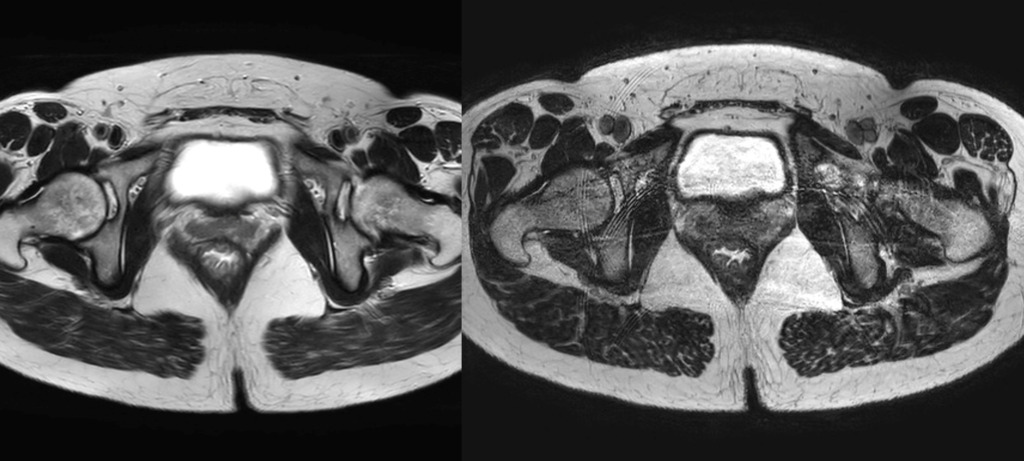

従来の撮像プロトコルでは、T2WIの軸位(Axi)および斜位冠状(obl-Cor)画像を中心に3mm厚で撮影されていました。しかし、2020年以降、多くの施設で共同研究用の新プロトコルが採用され、撮像技術は大きく進化しています。近年では**高分解能撮像(High Resolution: 0.6mm×0.6mm)**が可能となり、微細な構造の識別がより明確になっています。また、撮像時間の短縮と高画質化を両立させるため、SSFSE(Single Shot Fast Spin Echo)にDLR(Deep Learning Reconstruction)を組み合わせた撮像が導入され、骨盤全体像をわずか30秒以内で取得できるようになっています。さらに3D-T2WでもDLRを併用することで、三次元的な再構成による腫瘍の立体的把握が容易となりました。

※当院のMRI画像

こうした技術的進歩により、MRIによる直腸がんの評価は単なる「腫瘍の存在診断」から、「手術戦略立案のための機能的画像診断」へと進化してます。特に、**腫瘍の短軸像(short-axis view)**は臨床的に最も重要であり、CRM(circumferential resection margin:環周切除断端)やEMVI(extramural vascular invasion:血管外浸潤)といった予後因子の評価において必須の情報を提供できます。